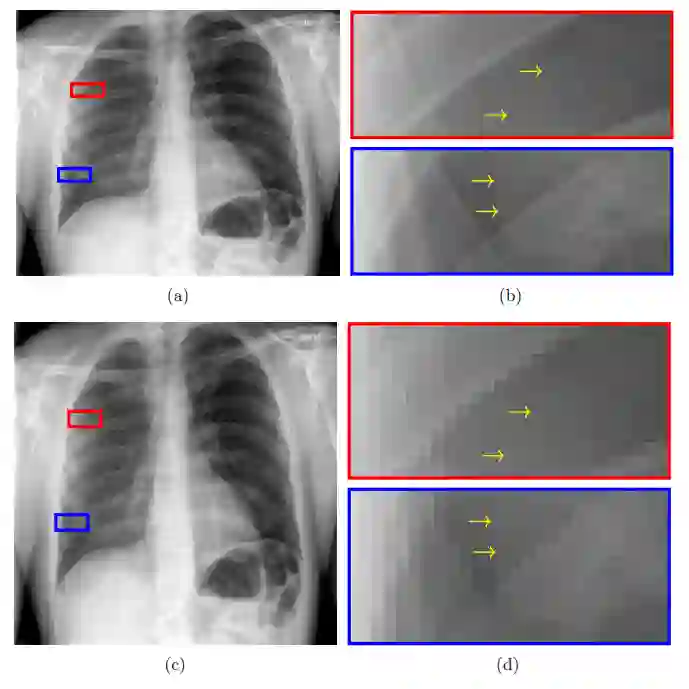

图 2.3:基于气胸的高分辨率和低分辨率胸部 X 光片的比较。 (a) 以 2828 × 2320 像素的全图像尺寸显示原始胸部 X 光片。在 (b) 中,显示了 (a) 的两个区域,放大了 10 倍。黄色箭头指向胸膜边缘,表示气胸。为了比较,(c) 显示 (a) 通过双线性插值缩小到 256 × 256 像素的图像大小。 (d) 显示与 (b) 相同的放大区域,胸膜边缘不再可见。示例图像取自 OpenI 数据集 [Demner-Fushman et al., 2016] (ID: 3378)。